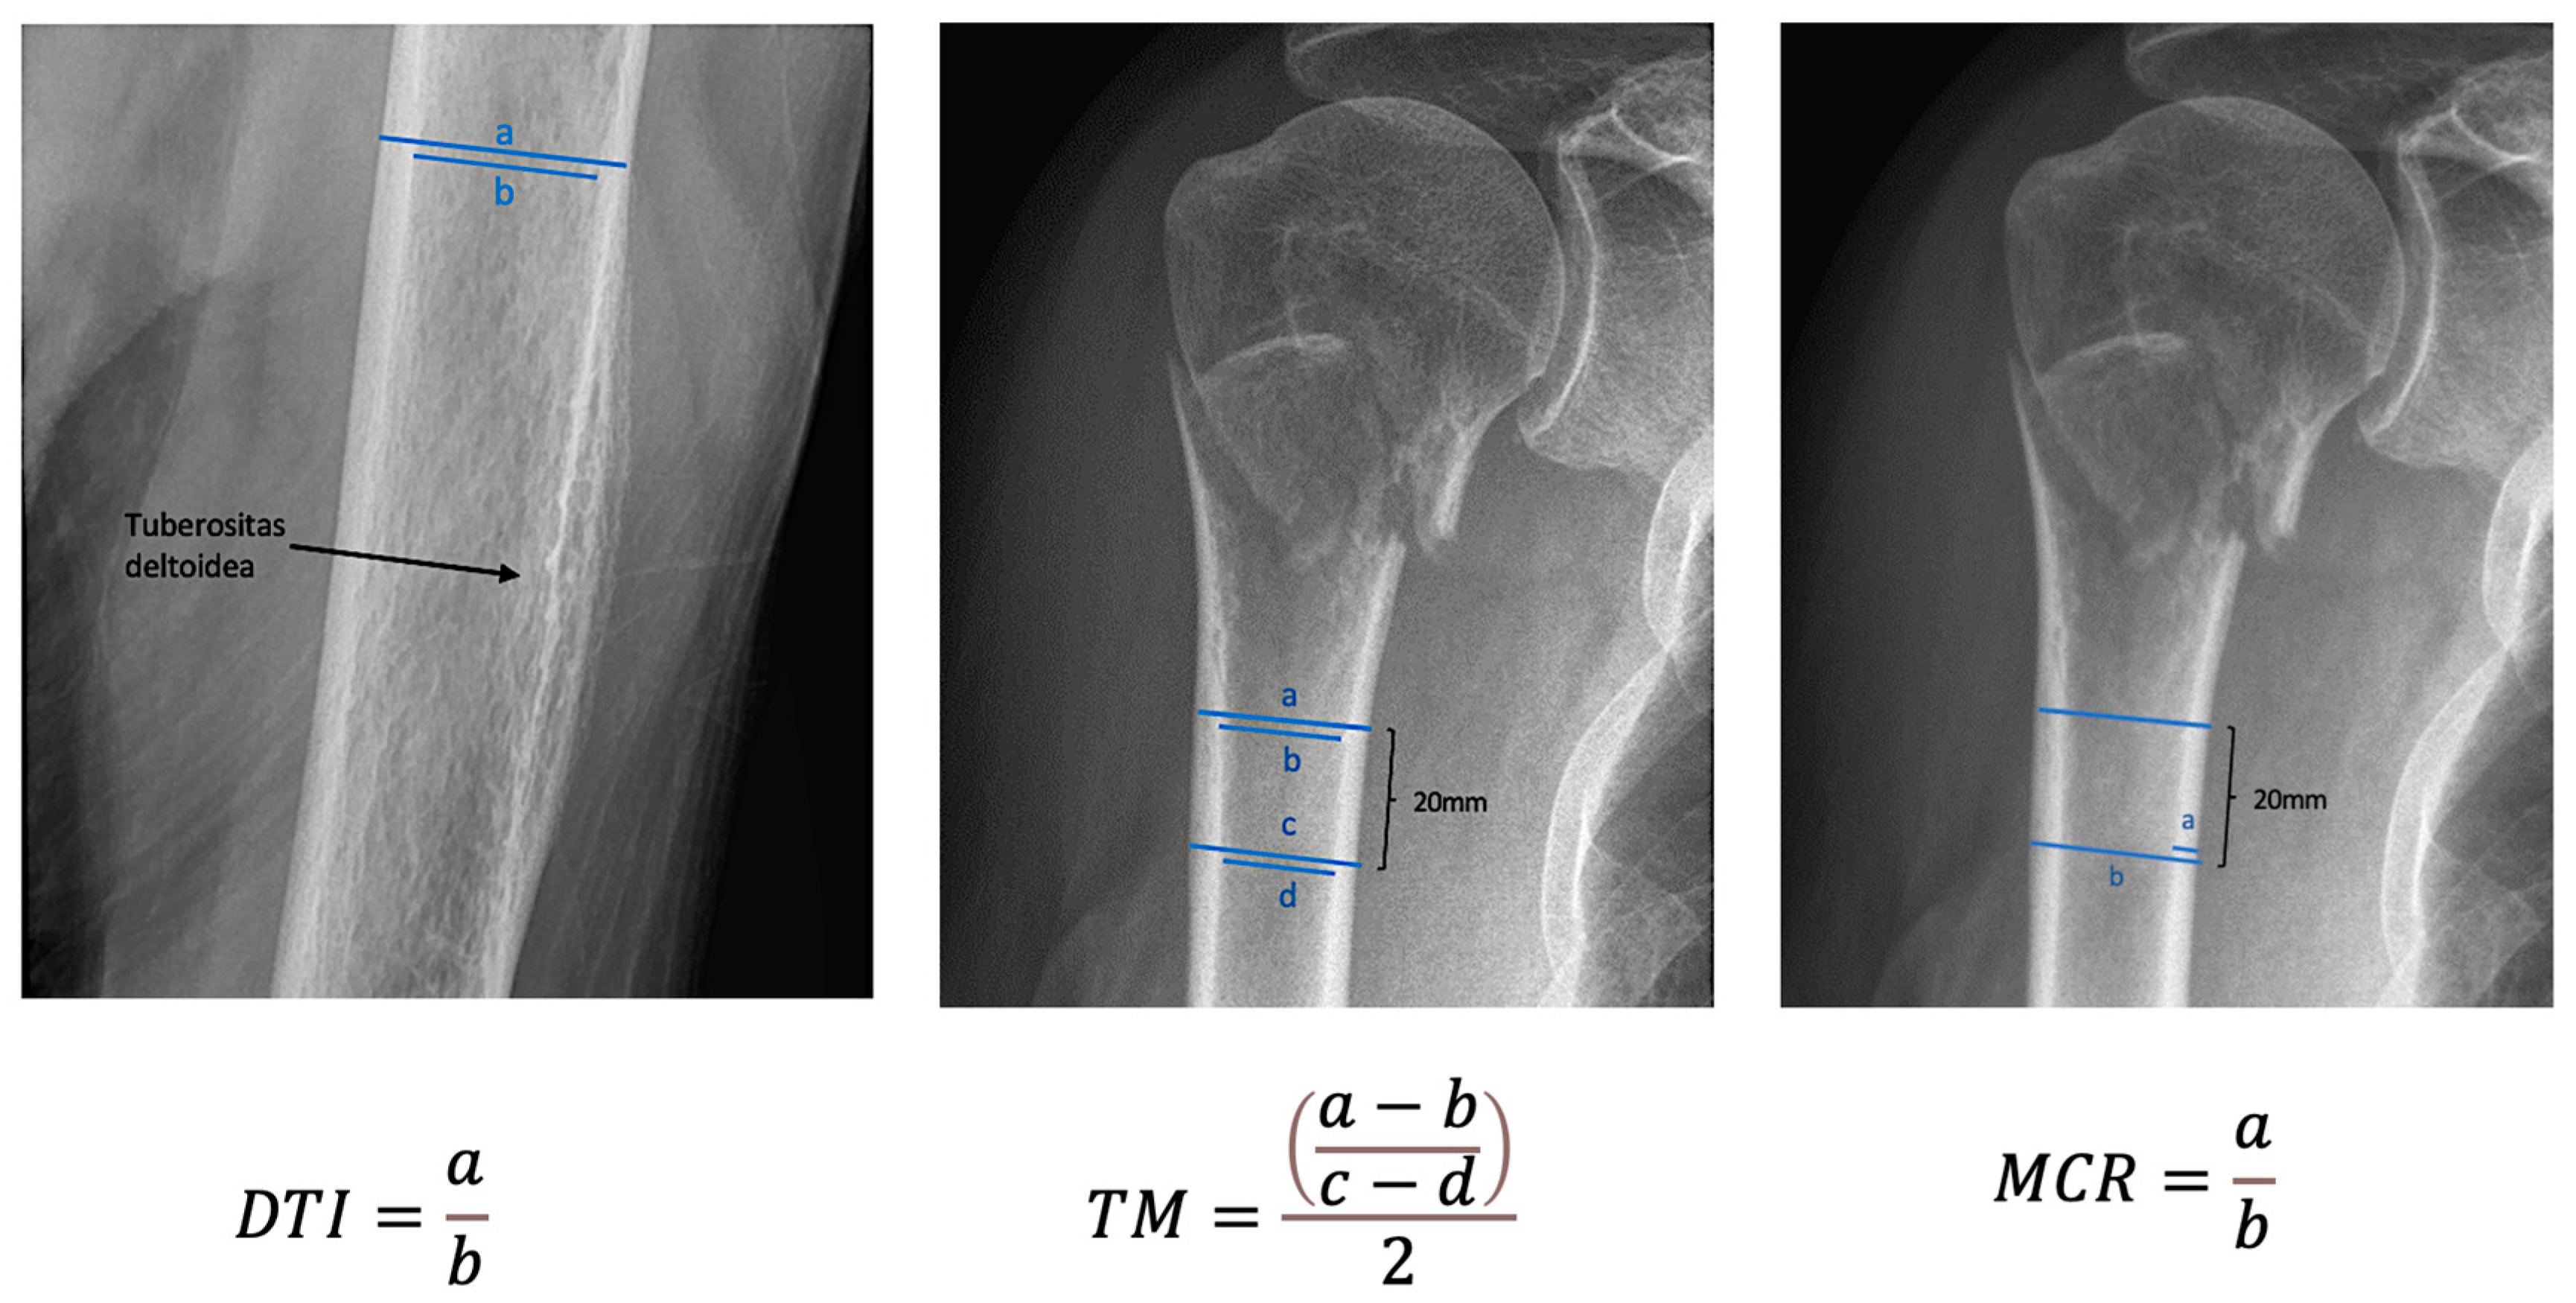

| DTI | 1.4 | 1.2–1.9 | 0.1 |

| TM | 6.2 | 3.1–13.5 | 1.6 |

| MCR | 0.2 | 0.1–0.3 | 0.03 |